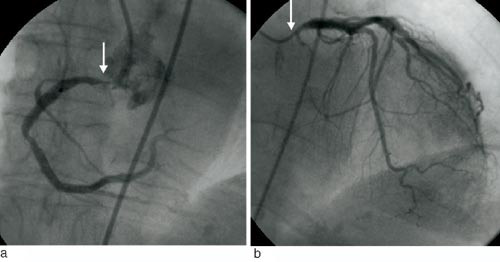

Pasient 1. 73 år gammel kvinne med kjent hypertensjon, ellers frisk. Hun fikk akutt innsettende retrosternale brystsmerter med utstråling til halsen, og var sirkulatorisk ustabil med hypotensjon. Legebemannet ambulanse sendte prehospitalt EKG til hjerteovervåkingen 1/2 time etter debut av brystsmerter (fig 1). EKG ble tolket som forenlig med akutt nedreveggsinfarkt, pasienten fikk acetylsalisylsyre og heparin, og ble deretter kjørt til angiografilaboratoriet for primær angioplastikk. Ved kontrastinjeksjon i høyre koronararterie fant man imidlertid en A-disseksjon med aortainsuffisiens grad 3. I tillegg fant man en høygradig hovedstammestenose både på høyre og venstre side (fig 2). Pasienten ble derfor umiddelbart operert med bypass til høyre koronararterie, man valgte peroperativt ikke å legge bypass til venstre koronararterie. Postoperativt protrahert forløp, overflyttet lokalsykehus for mobilisering.

Pasient 4. 49 år gammel frisk mann. I forbindelse med pushup-øvelser fikk han brystsmerter, som avtok noe ved innleggelse. EKG samt flere sett myokardmarkører var normale. Røntgen thorax var normalt, spesielt var det ingen breddeøkning av mediastinum. Dagen etter viste imidlertid EKG nytilkommet, grensesignifikant ST-elevasjon i nedreveggsavledninger sammenliknet med innkomst-EKG. Påfølgende ekkokardiografisk undersøkelse av hjertet gav mistanke om A-disseksjon, og dette ble verifisert ved angiografi. Koronararteriene var normale. Pasienten ble samme dag operert og kunne senere utskrives uten sekvele.